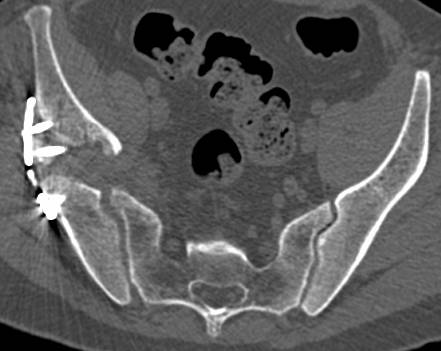

[Ortho] перелом правой половины таза

высылаю дополнительно  сканы.